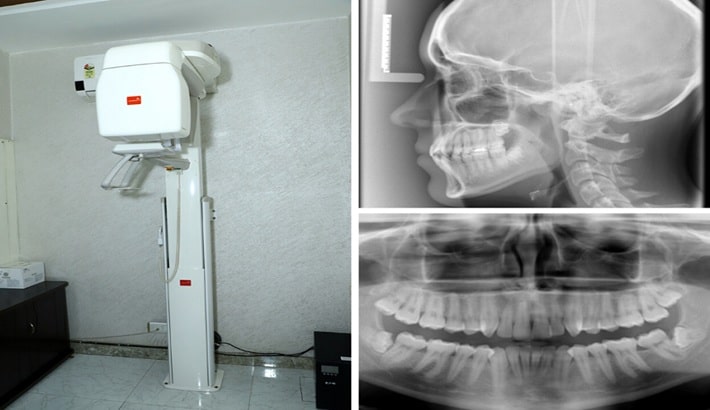

تفاوت عکس opg شیراز با سیتیاسکن دندان (کدام یک برای شما مناسبتر است؟)

عکس opg دندان | تفاوت عکس opg شیراز با سیتیاسکن دندان

وقتی فرد با درد دندان، نیاز به ایمپلنت، احتمال عفونت یا مشکلات مفصل فک به دندانپزشک مراجعه میکند؛ معمولاً اولین توصیه تهیه یک تصویر تشخیصی است. در شیراز، بیماران اغلب بین دو روش پرتکرار یعنی عکس OPG شیراز و سیتیاسکن دندان دچار تردید میشوند؛ زیرا تصور میکنند هردو یک هدف را دنبال میکنند. در حالیکه این دو روش تفاوتهای اساسی از نظر دقت، کاربرد، هزینه، سرعت و میزان اشعه دارند؛ همچنین انتخاب بین آنها باید بر اساس شرایط بیمار انجام شود. عکس opg شیراز تصویری دوبعدی و گسترده از فک، ریشهها، سینوسها و دندانها ارائه میدهد و برای بررسی اولیه بهترین انتخاب است. اما سیتیاسکن دندان، بهویژه CBCT، یک تصویر سهبعدی با جزئیات بسیار بالا تولید میکند؛ این نوع تصویربرداری برای تصمیمگیریهای حساس مانند جراحی، ایمپلنت یا بررسی شکستگیهای ظریف ضروری است. مرکز تابا این امکان را فراهم کردهاند که بیمار دقیقاً همان روشی را انجام دهد که براساس تشخیص پزشک برایش مناسبتر است.

تفاوت در نوع تصویر و میزان جزئیات میان OPG و سیتیاسکن

عکس OPG شیراز تصویری دوبعدی و وسیع از هر دو فک ارائه میدهد. این تصویر برای ارزیابی کلی وضعیت دهان، تشخیص دندانهای نهفته، بررسی شکل فک، تحلیل سینوسها و مشاهده ریشه دندانها مناسب است. گرچه OPG نمیتواند عمق و ضخامت استخوان را مانند تصاویر سهبعدی نشان دهد، اما برای شروع مسیر درمان بسیار ارزشمند است؛ زیرا دندانپزشک در یک نگاه میتواند تمامی ساختارهای مهم دهان را ارزیابی کرده و مشکلات اولیه را شناسایی کند. یکی از دلایل محبوبیت عکس OPG در شیراز ، هزینه پایین، سرعت بالا و مقدار بسیار کم اشعه آن است. به همین دلیل، بسیاری از پزشکان در اولین مراجعه بیمار، قبل از درخواست روشهای دقیقتر، تهیه OPG را لازم میدانند.

تصویر سهبعدی سیتیاسکن؛ انتخاب مناسب برای درمانهای حساس و پیچیده

سیتیاسکن دندان یا CBCT تصویری سهبعدی تولید میکند که شامل حجم، عمق، تراکم استخوان و موقعیت دقیق ساختارهاست. این تصویر به دندانپزشکان اجازه میدهد کوچکترین جزئیات را بررسی کنند، چیزی که در OPG قابل مشاهده نیست. در مواردی مانند برنامهریزی برای کاشت ایمپلنت، تعیین محل دقیق عصب فک و تشخیص کیستهای پیچیده تنها CBCT اطلاعات لازم را فراهم میکند. این روش اشعه بیشتری نسبت به OPG دارد و هزینه آن نیز بالاتر است، اما ارزش آن در روشهای درمانی حساس بسیار بالا است. مرکز تصویربرداری پزشکی تابا در شیراز از دستگاههای CBCT نسل جدید استفاده میکند تا تصویرها با کمترین خطا و دقیقترین جزئیات ثبت شود.

تفاوت در کاربردهای درمانی و تشخیصی OPG و سیتیاسکن

در بسیاری از موارد، نیازی به تصویربرداری سهبعدی نیست و همان عکس OPG شیراز کافی است. برای مثال، برای ارزیابی پوسیدگیهای گسترده، تشخیص دندان عقل نهفته، ارزیابی نیاز به ارتودنسی، بررسی عفونتهای اولیه ، OPG اولین و مناسبترین گزینه است. این روش سریع، بدون درد و کمهزینه بوده و با یک نگاه کلی وضعیت دهان را مشخص میکند. حتی در کودکانی که امکان بیحرکتماندن طولانی ندارند، OPG گزینهای بسیار مناسب و کماشعه است. همچنین برای بیمارانی که تنها قصد چکاپ دورهای دارند، استفاده از OPG منطقیتر و مقرونبهصرفهتر است.

موارد ضروری برای انجام سیتیاسکن و محدودیتهای OPG در تشخیص دقیق

در برخی موارد، عکسOPG شیراز به دلیل دوبعدیبودن قادر به نمایش جزئیات دقیق نیست. برای مثال، برای بررسی مسیر عصب فک پایین، تشخیص شکستگیهای ظریف، تحلیل دقیق سینوسها، تشخیص تودهها و… تنها CBCT اطلاعات کاملی ارائه میدهد. بیمارانی که سابقه جراحی، عفونتهای شدید یا دردهای مزمن مفصل دارند نیز معمولاً به سیتیاسکن نیاز پیدا میکنند. به همین دلیل، در مرکز تابا معمولاً پس از مشاهده OPG و در صورت نیاز به بررسی دقیقتر، CBCT برای تکمیل فرآیند انجام میشود.